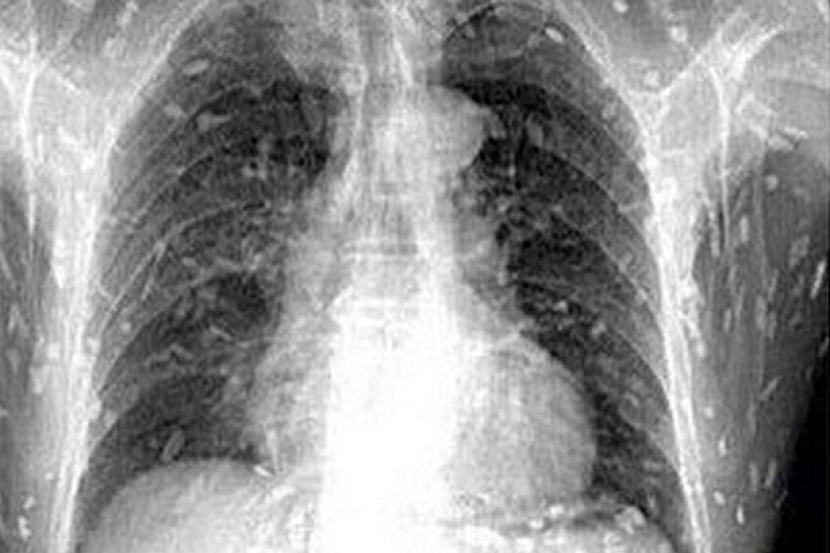

Hasil imbasan doktor mendapati, setiap ruang tubuh badan lelaki terbabit dipenuhi cacing yang berpetonsi menjadi pembunuh dalam tempoh terdekat.

Pemeriksaan awal doktor mendapati, cacing itu kini membiak dengan pantas dan menganggu usus pesakit.